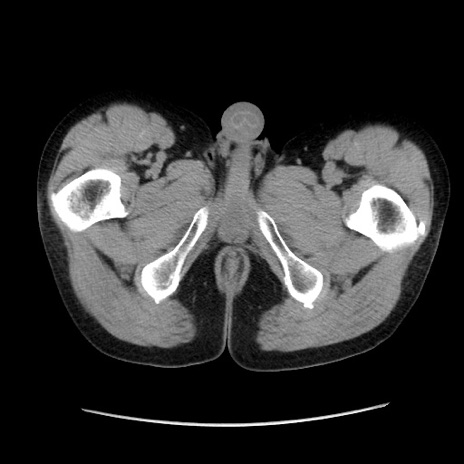

冠状断像

【症例】40歳代 男性

【主訴】腹痛

【現病歴】4時間ほど前に電車に乗車中に臍部上より腹痛出現。徐々に増悪し起立困難となり、救急外来受診。生ものは数日食べていない。今朝お雑煮を食べた。

【身体所見】BT 36.8℃、BP 117/84mmHg、HR 91/min、SpO2 97%、苦悶様、腹部:臍上部広範囲圧痛あり、反跳痛±

【データ】WBC 8100、CRP 0.03